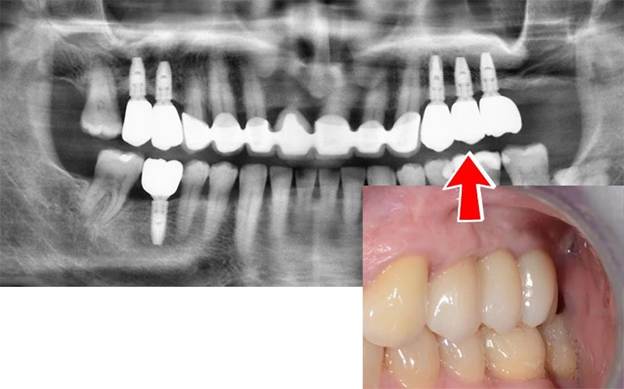

Към тази група трябва да причислим и зъбните импланти tissue level на Straumann. Да вярно е, че тези импланти са създадени преди bone level имплантите, но последните статистически данни и научни изследвания показват, че те имат своето място при определени условия в задната част на зъбната редица – ниска, но по-широка кост. С тяхна помощ може, да се избегне sinus lift в горна челюст или вертикална костна аугментация в долна челюст.

- Наличният обем кост – задължително 3D изследване. Ако е необходимо, се извършва прилагане на предварителни аугментационни процедури за увеличаване обема на костта.

- Обемът и качеството на меките тъкани около бъдещия имплант – гингива / венецът /. Те пазят костта около импланта. Те са гаранцията за дълготрайния успех и естетика. Създават сe при необходимост, желание и възможности с мекотъканна, муко-гингивална хирургия.

Ако за предварителните и допълнителни процедури не се говори, това може да означава едно – тяхното непознаване и оттам невъзможност за прилагане. Именно от предварителните и допълнителните процедури зависи в около 70% от случаите качеството на лечението със зъбни импланти и неговата дълготрайност.

В крайна сметка Вие искате зъби, с които да живеете като нормални хора. Трябва да знаете, че има много хора, които имат импланти. Но нямат зъби, или пък повече никога няма да могат да бъдат лекувани с помощта на зъбни импланти, поради безвъзвратно загубения обем кост и меки тъкани от лошо лечение. Тези хора са обречени в най-добрия случай, да носят цял живот снемаеми протези с всичките им недостатъци.